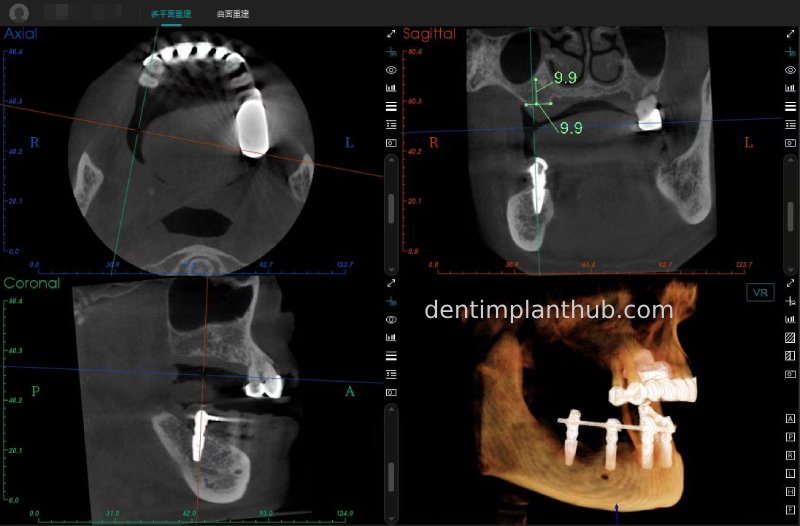

A review of the CBCT on 6/10/23 was more promising and a surgical plan was subsequently drawn up.

46

44

42

32

34

36

General schematic of the surgical programme

Detailed list of implant types and composite abutments to be prepared.

46 tooth position, implant model number 4810, RC series straight composite abutment;

44 tooth position, implant model number 4110, RC series straight composite abutment;

42 tooth position, implant model number 4110, RC series straight composite abutment; alternate implant model number 3310, alternate NC series straight composite abutment;

32 tooth position, implant model number 4110, RC series straight composite abutment; alternate implant model number 3310,. Alternate NC Series Straight Composite Abutment;

34 Dental Position, Implant Model No. 4110, RC Series Straight Composite Abutment;

36 Dental Position, Implant Model No. 4808, RC Series Straight Composite Abutment;